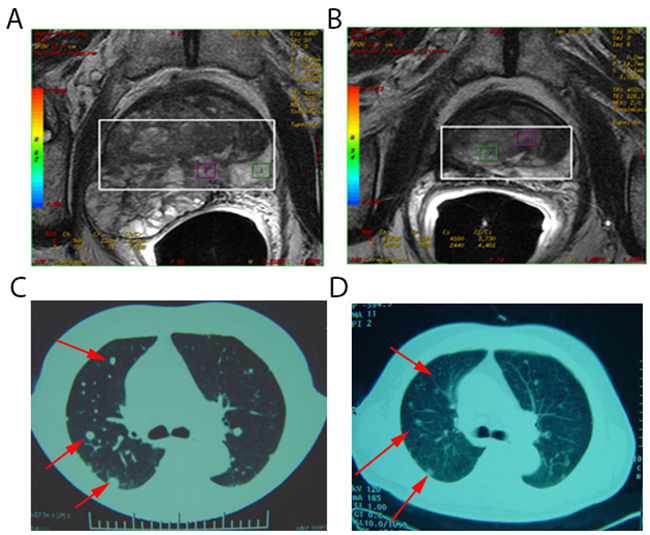

Here, the abscopal effect was also detected after cryoablation of metastatic cancer where localized treatment causes shrinking of lung metastases outside the scope of the localized treatment (Figure 1). Although this phenomenon is extremely rare, its effect on cancer can be stunning, leading to the disappearance of malignant tumors throughout the entire body. Such success has been described for a variety of cancers, including parietal pleura adenocarcinoma [11], musculoskeletal tumors [12], and papillary fibroelastoma [13]. Nonetheless, scientists are not certain how the abscopal effect works to eliminate cancer in patients. Clinical studies on breast cancer suggest that the effect may depend upon activation of the immune system [14]. In a case study from the Memorial Sloan-Kettering Cancer Center on metastatic melanoma [15], these dynamic changes in tumor-directed antibody levels and immune cell populations were seen during the abscopal effect.

Figure 1: Spontaneous regression of lung metastases after cryoablation for metastatic prostate cancer. (A) Pelvic magnetic resonance imaging of a 78-year-old man with metastatic prostate carcinoma (Stage T3bN0M1c). This lesion was treated with cryoablation. (B) Pelvic magnetic resonance imaging 1 month post-treatment appeared inactive. (C) Computed tomography scans of pulmonary metastasis of the patient before treatment revealed multiple metastases in lung tissues (red arrow). (D) Computed tomography scans of pulmonary metastasis of the patient 1 month post-treatment indicated regression of lesions in lung tissues (red arrow).

As early as the 1970s [25], remission of metastases after cryosurgery in prostatic cancer (defined as an immunologic response) has been recognized. Bayjoo P and colleagues [26] have reported enhanced NK cytotoxicity following cryosurgery of an implanted liver tumor in rats. Hamad GG et al. [27] also demonstrated the transient immune response to cryosurgery in an experimental model. Cryoablated tumors in glioma mouse models induced an antitumor cellular immunological response, which increased the percentage of CD3+ T and CD4+ T cells in blood as was the case for NK cells [28]. During our clinical research, we also observed this phenomenon (Figure 1) induced by cryoablation of prostate cancer (defined as the abscopal effect).